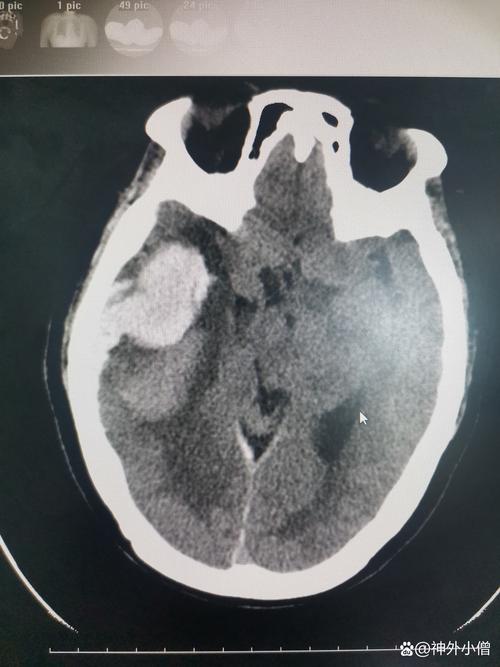

(图片来源网络,侵删)- 普通平扫CT:它主要是看密度变化,在发病超早期(6小时内),可能看不到明显异常,几小时到几天后,坏死的脑细胞会因为水肿而密度变低,这时才能看到低密度的梗死灶,但它无法区分哪些是已经坏死的“核心区”,哪些是濒临死亡的“半暗带”,它只能看到一个“模糊”的梗死整体。